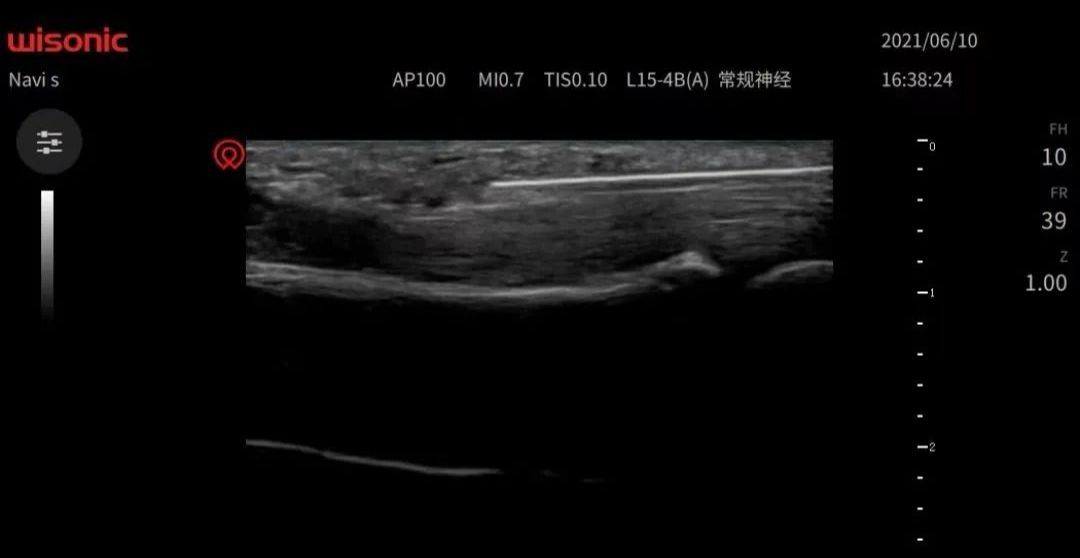

山西省煤炭中心医院已经获批“山西省超声可视化针刀培训中心”,系全国首家省级可视化针刀培训中心,将进一步推动我省乃至全国超声可视化针刀诊疗规范化、标准化、同质化,促进可视化微创诊疗技术水平的提升和发展。超声引导下针刀治疗就是可视化针刀微创技术,治疗的那根针就是针刀——由金属材料做成的在形状上似针又似刀的一种用具。其尾部为柄,体部为针,头部为刀。针刀虽小,作用很大,超声为针刀技术装上了“眼睛”,使针刀治疗更加精准、安全。可视化时代的针刀微创技术是针刀医生的GPS和“第三只眼”,它将术前明确诊断、术中精准引导靶点松解,术后进行评估,避免肌腱、神经、血管等组织损伤,减少治疗次数(每周一次)、缩短患者病程、保障医疗安全、大幅度提高临床效果

超声可视化针刀微创诊疗技术主要解决各类疼痛及偏瘫类疾病。一、脊柱疾病如颈椎病、腰椎间盘突出症等;关节疾病如膝关节骨性关节炎;各种软组织损伤如肩周炎、网球肘、梨状肌损伤;神经卡压如腕管综合征等疾病;腱鞘炎;鼻炎;带状疱疹等,主要原理:消炎(无菌性炎症);松解粘连;改善肌肉平衡。二、脑梗死、脑出血、脑外伤、脊髓损伤等引起的偏瘫、四肢瘫。主要原理:醒脑调衡;神经调控术;缓解或解除肌痉挛等。山西省煤炭中心医院